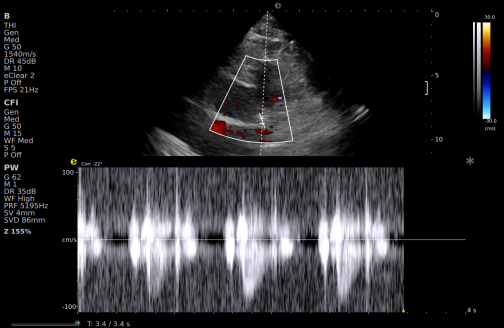

一例胸闷患者,临床采用无创冠脉超声作为初步评估手段,检查中发现:

彩色多普勒:敏感捕捉到局部血流加速现象;频谱多普勒:测得峰值血流速度明显升高,频谱形态异常。

频谱多普勒

基于超声提示的异常发现,临床为患者安排了冠脉CTA检查,结果显示前降支近段存在约45%狭窄,与超声提示的血流动力学改变高度一致。

这一病例体现了冠脉超声作为初筛工具的重要价值:它能够无创、实时地评估冠脉血流动力学状态,为后续是否需要进一步影像检查提供重要参考。超声与CTA的协同应用,既能评估结构变化,又能反映功能状态,为临床诊断提供了更全面的信息。